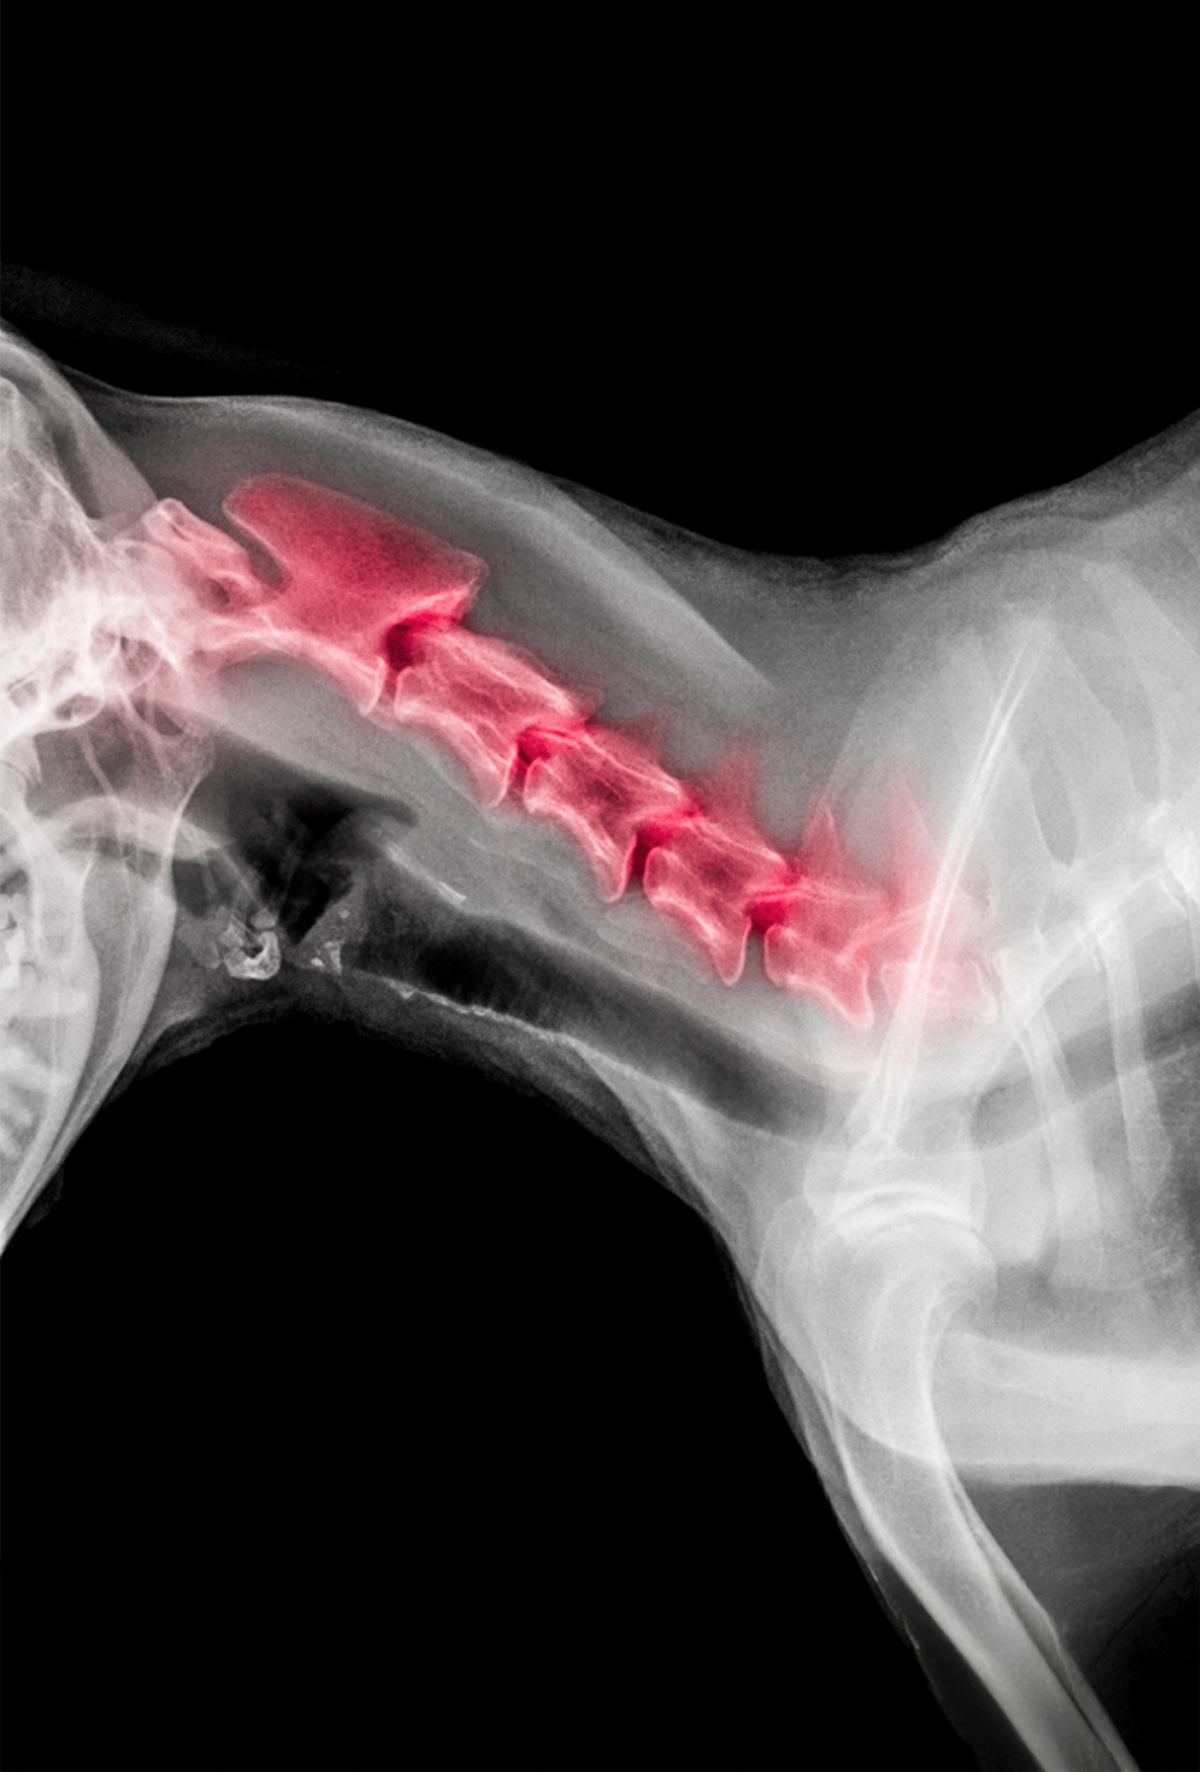

Wobbler sendromu

Wobbler sendromu çok ciddi bir hastalıktır ve ilerlediği takdirde çoğu kez daralmanın oluştuğu bölgeden itibaren tam felce neden olur.